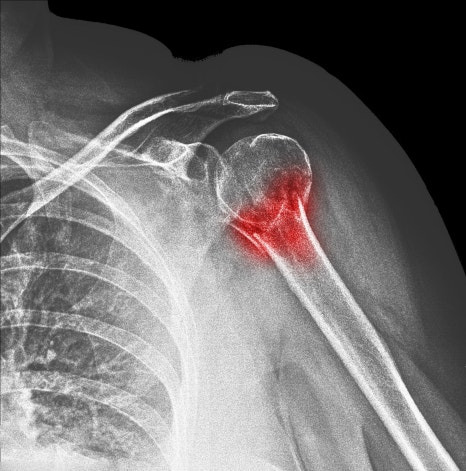

마지막으로 외상성 손상도 있습니다. 넘어지면서 팔을 짚거나 갑작스럽게 무거운 물건을 들었을 때 힘줄이 찢어질 수 있습니다.

이처럼 다양한 원인이 겹치면서 수원회전근개파열이 발생하게 됩니다.

어깨 통증은 흔하게 나타나는 증상이지만 그 원인은 다양합니다. 특히 팔을 들 때 통증이 반복되거나 밤에 더 심해지는 경우라면 수원회전근개파열과 같은 어깨 힘줄 손상을 고려해 볼 필요가 있습니다.